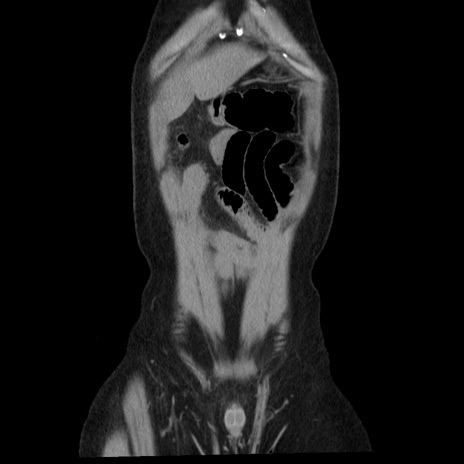

症例29(冠状断像)

【症例】40歳代男性

【現病歴】2日前から胃痛あり。徐々に周期的な激痛に変化した。本日になっても激痛があるため受診。

【身体所見】意識清明、BT 38-39℃台あり、腹部:膨満、やや硬、右下腹部に圧痛あり。

【データ】WBC 8500、CRP 23.26